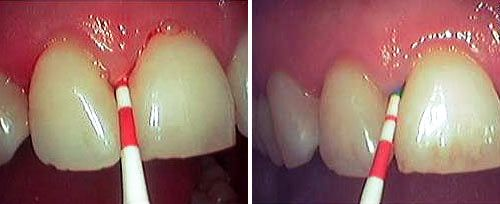

去龋

相对传统手机减少了因机械摩擦导致的热损伤,大大降低痛感和术后不适感,尤其适合于儿童、较为敏感的成人。

口腔激光怎么治疗口腔特色诊疗——激光治疗_https://www.jmylbn.com_新闻资讯_第2张

激光去龋前后对比图